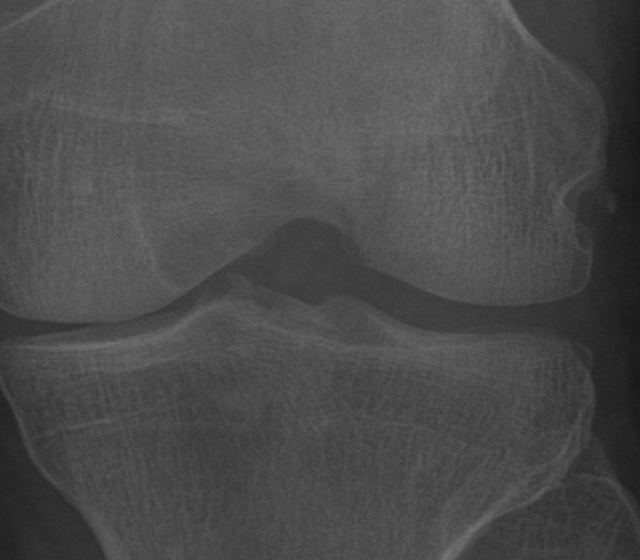

Knee OA develops gradually over years and progresses in stages. In general, the severity of knee OA is divided into five stages. The first stage (stage 0) corresponds to normal healthy knee and the final stage (stage 4) corresponds to the most severe condition (see Figure 2). The most commonly used systems for grading knee OA are the International Knee Documentation Committee (IKDC) system, the Ahlback system, and the Kellgren & Lawrence (KL) grading system. The other widely used non-radiographic knee OA assessment system is WOMAC666Western Ontario and McMaster Universities Osteoarthritis Index, which measures pain, stiffness, and functional limitation. The public datasets, the OAI and the MOST used in this work, are provided with the KL grades and they are used as the ground truth to classify the knee OA X-ray images.

Refer to caption

Figure 2: The Kellgren and Lawrence grading system to assess the severity of knee OA.

The KL grading scale was approved by the World Health Organisation as the reference standard for cross-sectional and longitudinal epidemiologic studies [7, 22, 24, 25]. The KL grading system is still considered the gold standard for initial assessment of knee osteoarthritis severity in radiographs [1, 5, 6, 7]. Figure 2 shows the KL grading system. The KL grading system categorizes knee OA severity into five grades (grade 0 to 4). The KL grading scheme for quantifying knee OA severity from X-ray images is defined as follows [1, 5]:

• Grade 0 : absence of radiographic features (cartilage loss or osteophytes) of OA.

• Grade 1 : doubtful joint space narrowing (JSN), osteophytes sprouting, bone marrow oedema (BME), and sub-chondral cyst.

• Grade 2 : visible osteophytes formation and reduction in joint space width on the antero-posterior weight-bearing radiograph with BME and sub-chondral cyst.

• Grade 3 : multiple osteophytes, definite JSN, sclerosis, possible bone deformity.

• Grade 4 : large osteophytes, marked JSN, severe sclerosis, and definite bone deformity.